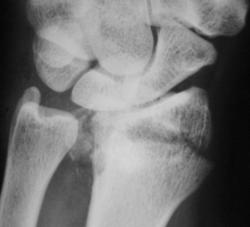

Маловато будет. Дополняю... Со смещением к тылу под углом и по ширине, плоскость эпифиза лучевой кости открыта к тылу под углом *** градусов (стояние отломков неудовлетворительное). Разрыв дистального луче-локтевого сустава.

Отвечаю как коллеге. ///Что есть что? Когда можно говорить о неудовлетворительном или наоборот?/// Точных данных под рукой нет, очень велика доля субъективизма. Общее правило: "Ну, не нравится мне это!!!". Все смещения по ширине просто отмечаю, в долях (1/4, 1/3, 1/2) от поперечника кости, Главное, стояние оси. Угловые смещения до 10 градусов считаются допустимыми. Плоскость эпифиза лучевой кости в норме открыта кпереди под углом 5-10 град. Горизонтальное положение можно считать допустмым. Небольшой наклон плоскости эпифиза кзади - можно считать относительно допустимым, но должен отмечаться в протоколе http://www.radiomed.ru/content/travma-pierielom-biez-smieshchieniia-kostnykh-otlomkov. Представленный случай ни в какие ворота не лезет: тут верные 25 град., более того предположительная ось кисти проецируется за пределы заднего края лучевой кости.

Хирург не ошибся, перелом классический, "луча в типичном месте", как любят писать травматологи. Да еще и внутрисуставной, оскольчатый.